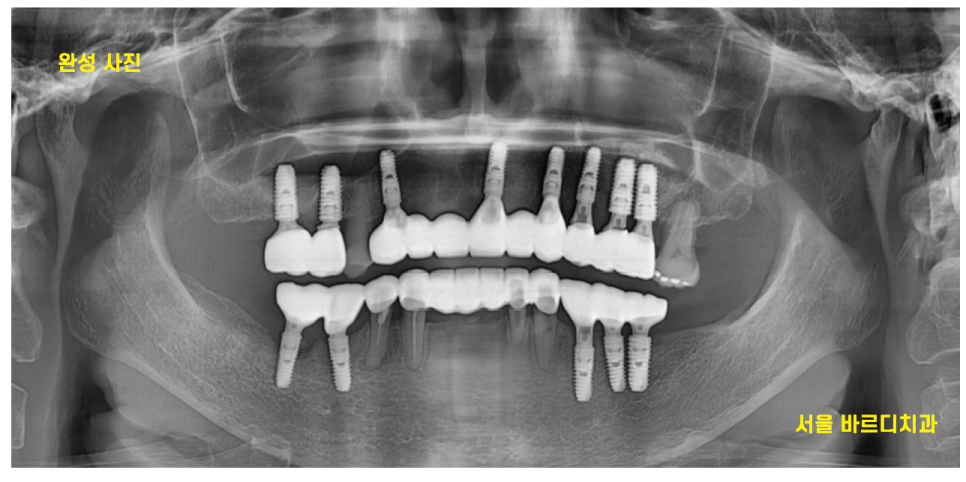

24.04.30

6개월 정도 지나

강동구 임플란트 치료 끝내드렸습니다.